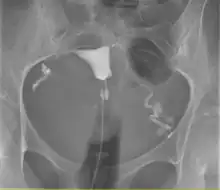

L'hystérosalpingographie est un examen de radiologie qui permet de visualiser l'utérus ainsi que son col et les trompes de Fallope.

Il y a d'abord un premier cliché sans l'ajout du produit de contraste qui permettra par la suite de visualiser l'appareil génital. On introduit ensuite le produit de contraste avec du matériel à usage unique. À l'aide d'une petite sonde positionnée dans le col utérin, un liquide à base d'iode est introduit dans l'utérus puis les trompes, il s'agit du produit de contraste, pour qu'il ne sorte pas immédiatement pas le col, on gonfle un ballonnet de manière que le produit remonte vers les trompes.

Des clichés sont pris en cours de remplissage de l'utérus et des trompes suivis d’un cliché tardif (20 minutes après la fin de l’examen).